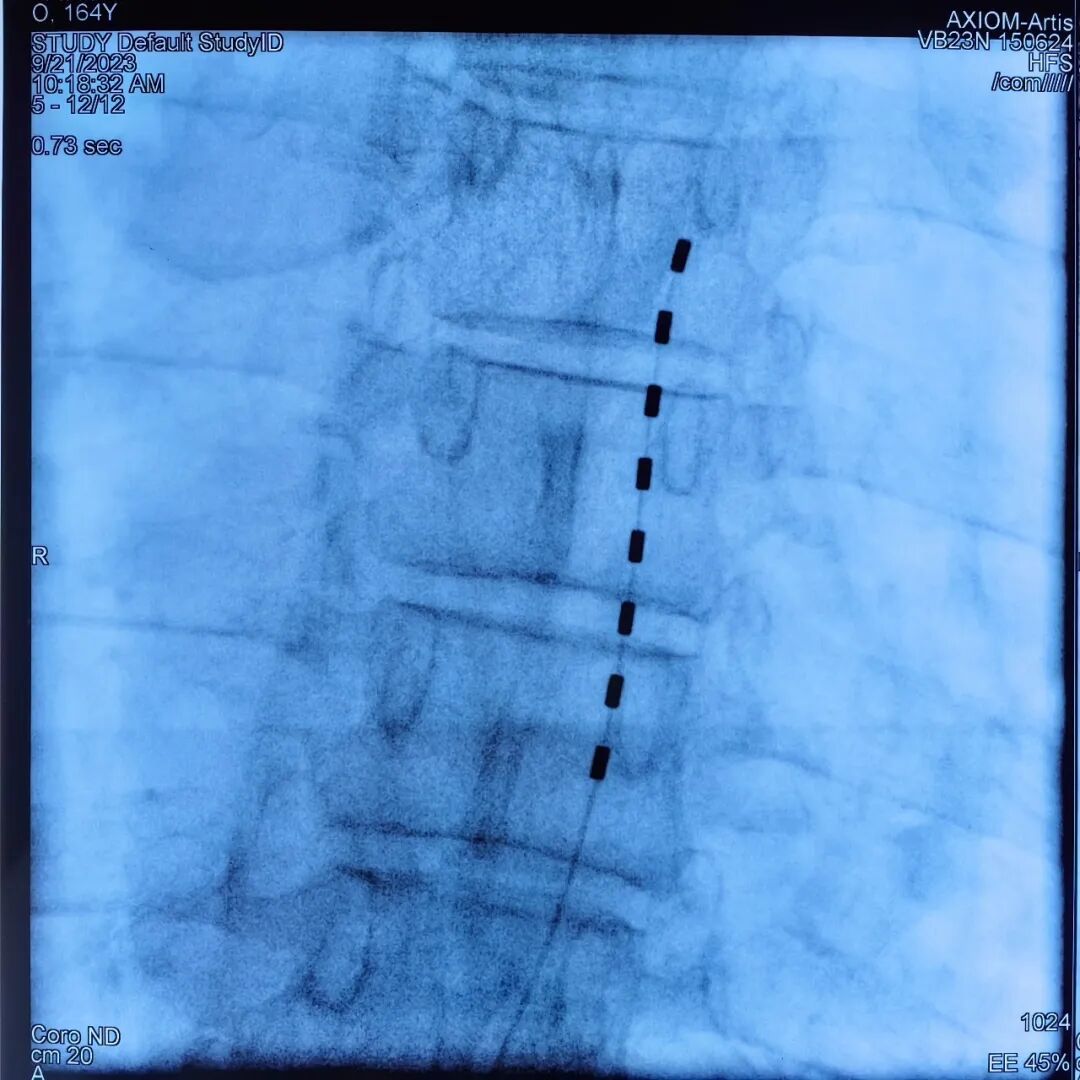

本次入选的国家主题案例,精准聚焦于带状疱疹后遗神经痛这一临床常见且极为棘手的慢性疼痛疾病。张广建及其团队基于丰富的临床实践,系统梳理并展示了如何将中医针灸、中药外治等传统医学精华,与脊髓电刺激疗法等西医技术进行深度融合与创新应用。

脊髓电刺激调控术